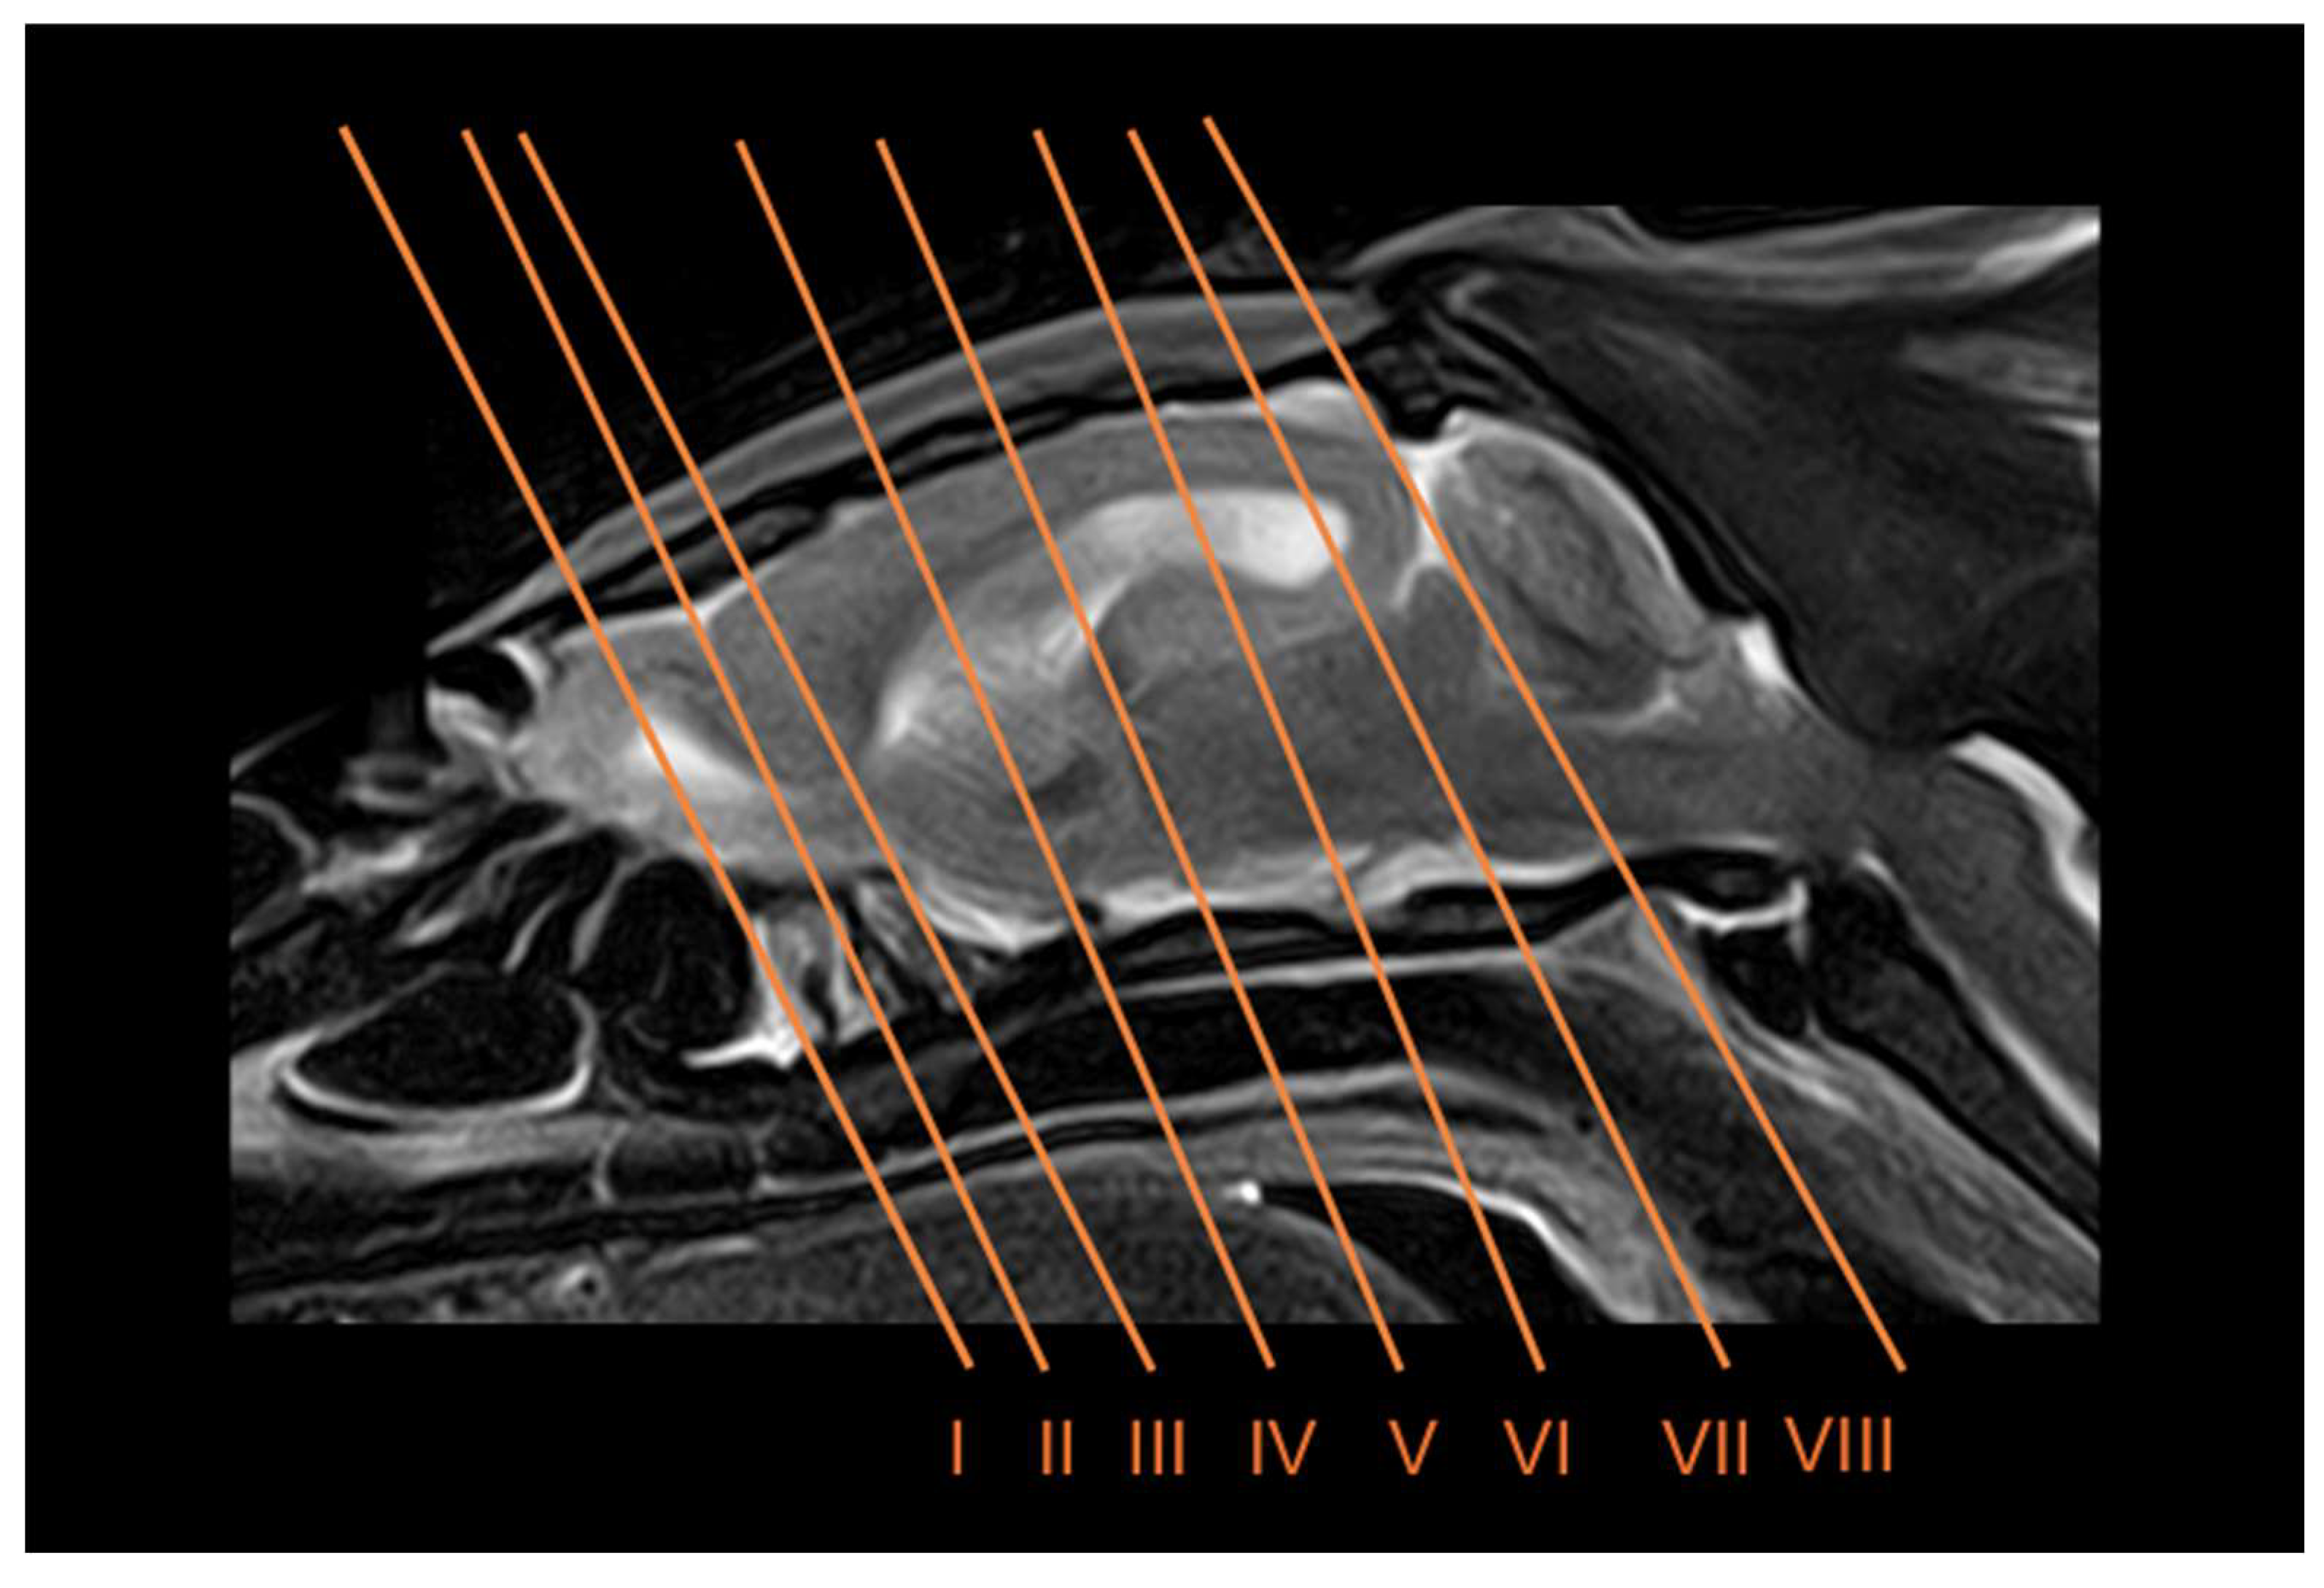

3.3. Magnetic Resonance Imaging (MRI)